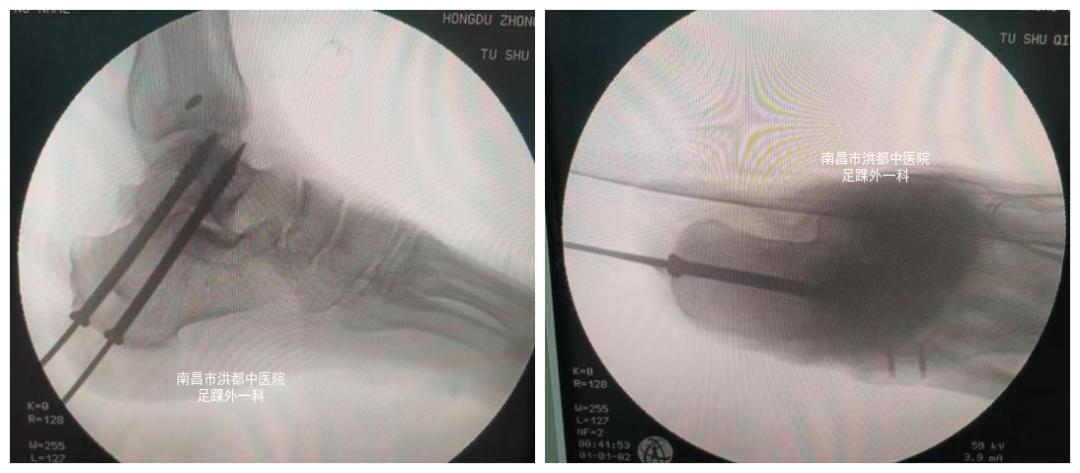

术中图

术中影像